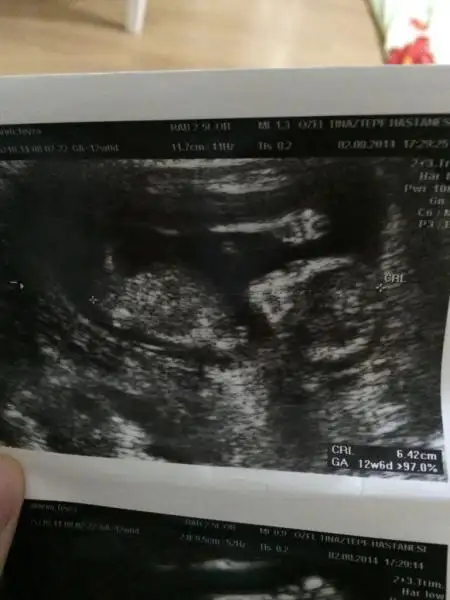

Kızımla biz allaha şükür iyiyiz resmi soran arkadaşlar vardı yüklüyorum maşallah giyin :)

Iki açıdanda fotosu var el sallıyor size

Saol canım inşallah görürsün sende eli kafasında yatıyo aynı bizim gibi eşimde bende öle yatarız mucize bu bence parmakları bile sayılıyo insanın inanası gelmiyor bazen Allah herkese yaşatsın bu duyguyu

14. Haftadayız canım büyüyoruz yavaş yavaş inşallah